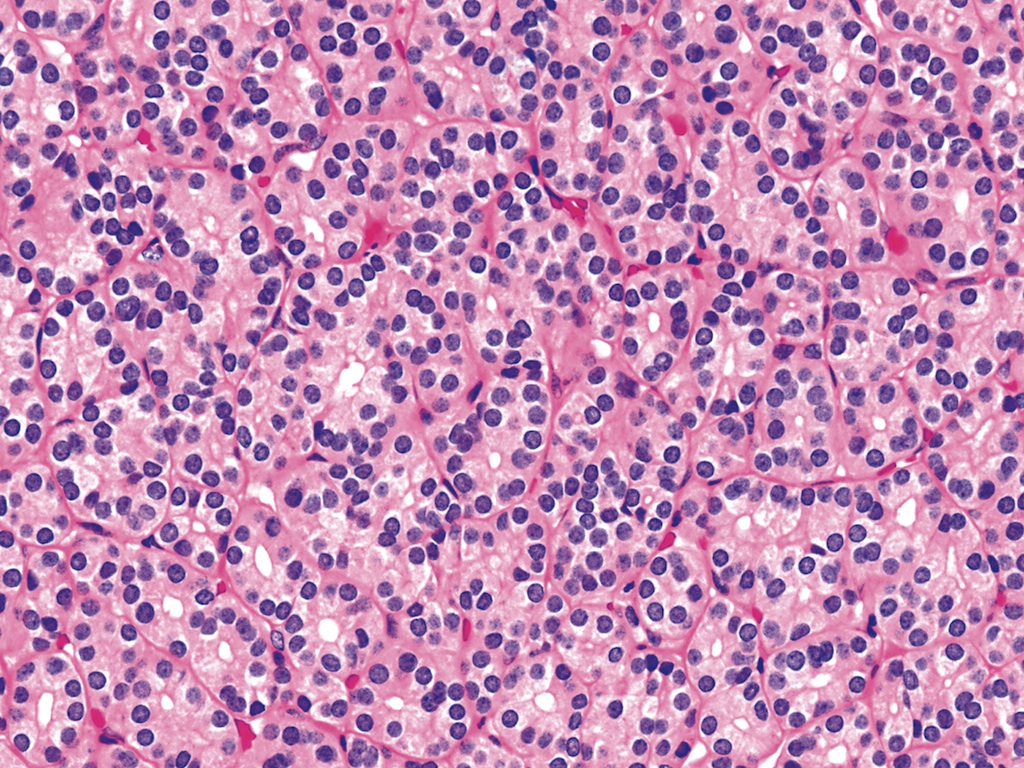

Microscopic (histologic) description

- Architecturally and cytologically different from surrounding gland

- Architectural patterns (can be seen in any combination)

- Solid / trabecular (embryonal): minimal or no colloid

- Cuboidal to low columnar cells

- Small round nuclei, smooth nuclear boundary, uniformly hyperchromatic or euchromatic, dense chromatin, absent nuclear features of papillary thyroid carcinoma, nuclear score 0 or 1 (JAMA Oncol 2016;2:1023)

- Inconspicuous nucleoli

- Rarely, lipid filled vacuoles in cytoplasm

- Mitoses are uncommon

- Scant stroma

Microscopic (histologic) images

Contributed by Shipra Agarwal, M.D., Andrey Bychkov, M.D., Ph.D., Mark R. Wick, M.D., Asmaa Gaber Abdou, M.D. and AFIP

Patterns:

Atypical adenomas: